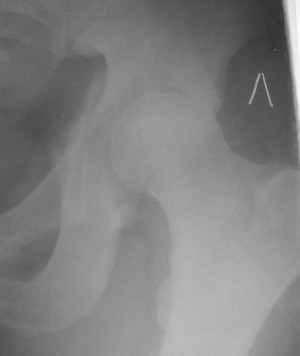

19/05/03

Больной 18 мая 2003 года в автоаварии получил перелом левой вертлужной впадины, вывих бедра. Госпитализирован в один из стационаров области.Вывих вправлен. В последствии бедро вывихивалось еще дважды. На консультацию был представлен снимок от 19.05.03г., больной переведен к нам 3.06.03г. Снимок при поступлении - перелом впадины, задне-верхний вывих бедра. 05.06.2003 г. выполнено открытое вправление вывиха левого бедра и остеосинтез стенки вертлужной впадины двумя винтами. Послеоперационный период без осложнений. Объем движений в левом тазобедренном суставе восстановился полностью. Выписан на амбулаторное лечение в удовлетворительном состоянии с рекомендациями 3 месяца ходить на костылях без нагрузки на оперированную конечность. На контрольных рентгенограммах левого тазобедренного сустава 13.10.2003 г. - признаки консолидации перелома; плотность, форма головки и состояние суставных поверхностей удовлетворительные. Разрешена дозированная осевая нагрузка, на конечность с использованием дополнительной опоры. 19.12.2003 г. больной обратился с жалобами на боли в левом тазобедренном суставе. На рентгенограммах левого тазобедренного сустава 19.12.2003 г., 20.02.04г. - асептичекий некроз головки бедра. 5.04.04г. - эндопротез. Сейчас ходит без трости, не хромает. Особенность эндопротезирования - при удалении винтов прослежена линия перелома заднего края впадины и предложено установить чашку несколько меньшего диаметра, чтобы она была покрыта несломанной частью.